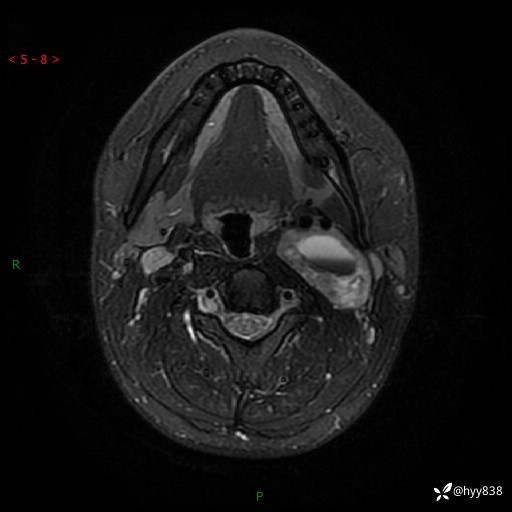

年轻小伙,发现左侧颈部肿物3年余,逐渐增大---结果公布~

现病史:患者约3年前因感冒发现左侧颈部长一肿物,约半个鸡蛋大小,无明显疼痛及其他不适,一直未行特殊处理。3个月前发现左侧颈部肿物变大,随后至当地市第二人民医院耳鼻喉科行左侧颈部彩超示:左侧颈部囊实混合性包块;喉部MPR示:左侧胸锁乳突肌内前方占位,累及左侧喉旁间隙,建议增强扫描。建议手术治疗。患者考虑。随后至我院肿瘤科就诊,行细胞学穿刺示:考虑血管源性肿瘤可能,建议进一步检查。建议至我院口腔科就诊,行颌面部MRI示:左侧颌下腺后方团状异常信号灶,建议增强。建议手术治疗。为求进一步治疗,门诊以“左侧颈部肿物”收入院。 起病以来,患者神志清、精神良好,饮食睡眠良好,大小便正常,体重未见明显变化。

颈部MRI平扫+增强